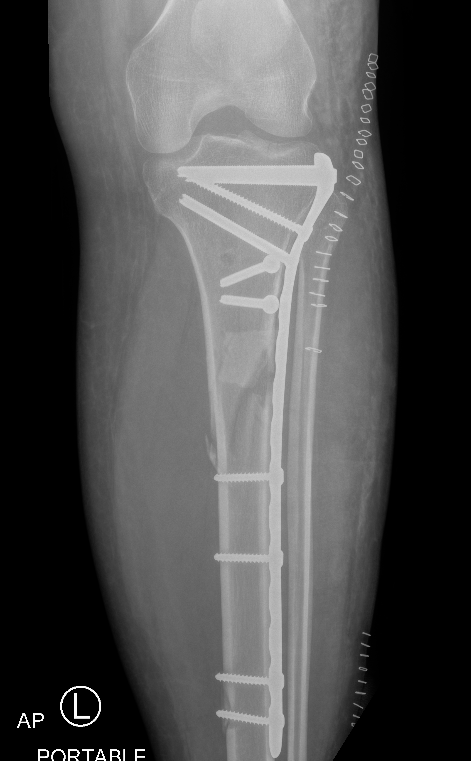

Plate Proximal Tibia Fractures

Nail + Plate fixation

Indications

Elderly

Allow early weight bearing

Technique